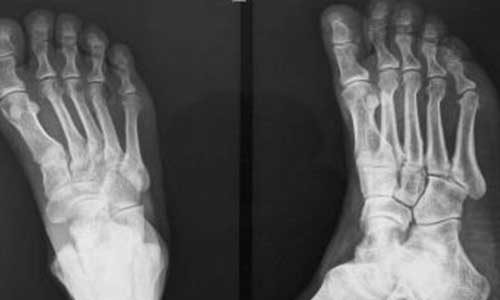

(图:唐大爷来院检查X光显示双脚关节变形且伴有痛风石)

X线检查:手足小关节尤其是第一跖趾关节的骨质破坏缺损、关节间隙狭窄、软组织偏心性肿胀。

(图:唐大爷治疗后X光检查脚趾关节变形已矫正,痛风石已消除)

在主治医生的治疗下,唐大爷血尿酸检查300umol/l ,已经恢复正常水平。手脚开始活动自如,可以正常生活,双手已经可以正常活动,关节形状恢复正常,手指僵硬胀痛反应也已消除,病情得到 。主治医生嘱咐唐大爷注意正常生活作息,维持体内尿酸平衡。